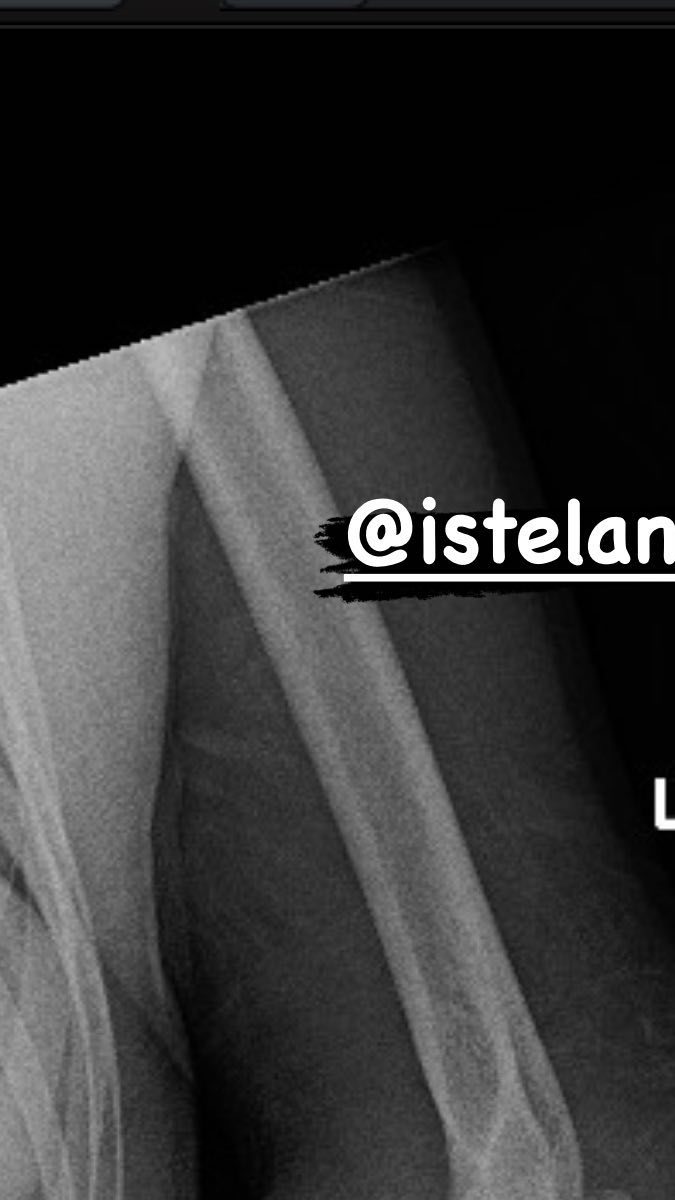

De acuerdo con una historia en Instagram de White, donde muestra la radiografía de la peleadora brasileña, el mandamás del UFC confirmó que se dislocó el codo. En la misma red social, Nunes agradeció los mensajes de apoyo de sus seguidores y expresó que regresará más fuerte.